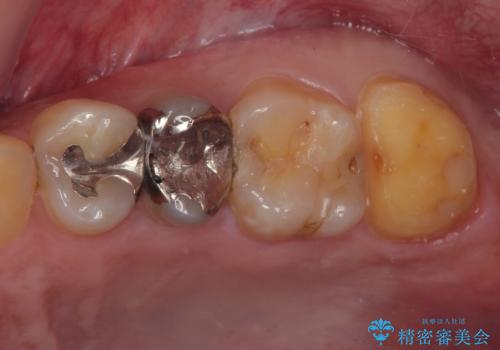

- 銀歯が何度も外れるとのことで来院された患者様です。

保険の金属の詰め物(メタルインレー)が適合性が悪い状態で入っていたので、詰め物も大きかったのでオールセラミッククラウンでの治療をご提案しました。

拡大鏡視野下で、金属の詰め物(メタルインレー)、虫歯の除去を行い、オールセラミッククラウンに適した形に整えました。